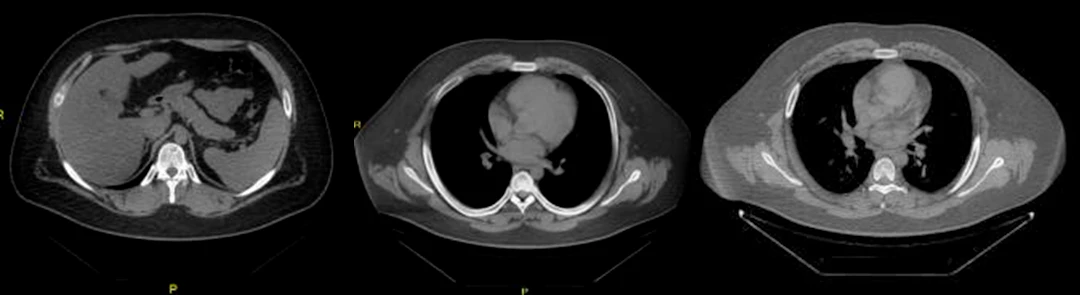

• Bietet Kunden einen 128-Zeilen-CT mit einer großen 76 cm Apertur

und verbessert die Bildauflösung auf 21 Lp/cm, was zu einer

genauen Krankheitsdiagnose und -behandlung beiträgt und

128-Zeilen-CT: Entwickelt für

Herzuntersuchungen

» Schneller 0,25-Sekunden-Herzscan

» EKG im Gantry integriert »

46 ms zeitliche Auflösung des Herzens »

Prospektive oder retrospektive Eingabe mit

bis zu vier Sektoren

Großer Durchmesser für vielfältige Anwendungen

» 76 cm Scanbereich/

250 kg Tischkapazität und 21 Lp/cm Auflösung sind problemlos möglich

» Bequeme Positionierung von adipösen Patienten ohne

Kompromisse bei Dosis oder Bildqualität.